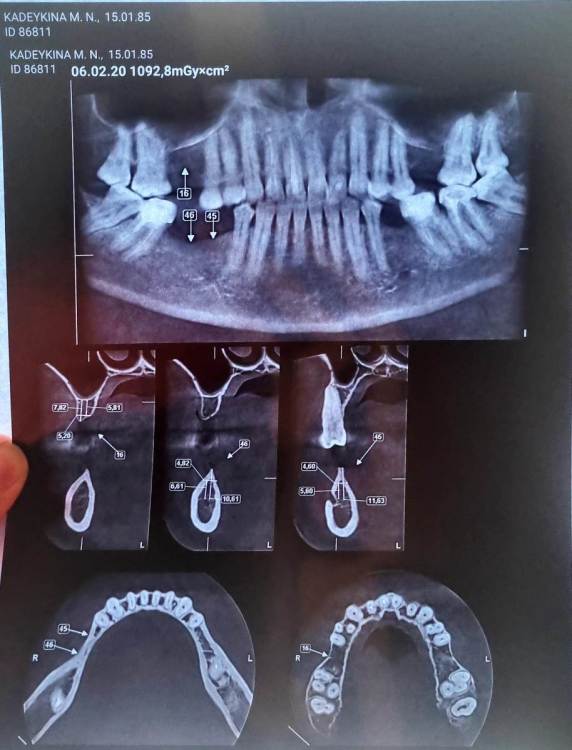

Здравствуйте, мне предстоит операция костная пластика альвелярного отростка 5, 6 зубы на н жний челюсти справа  , зубов там не было 20 лет. До нервно сосудистого пучка 4,5 мм. В анамнезе хроническая невралгия . скажите пожалуйста есть ли шанс восстановить десну с помощью пересадки костного блока своей кости ?

Были ли у кого пациенты с хронической невралгией тройничного нерва в анамнезе?